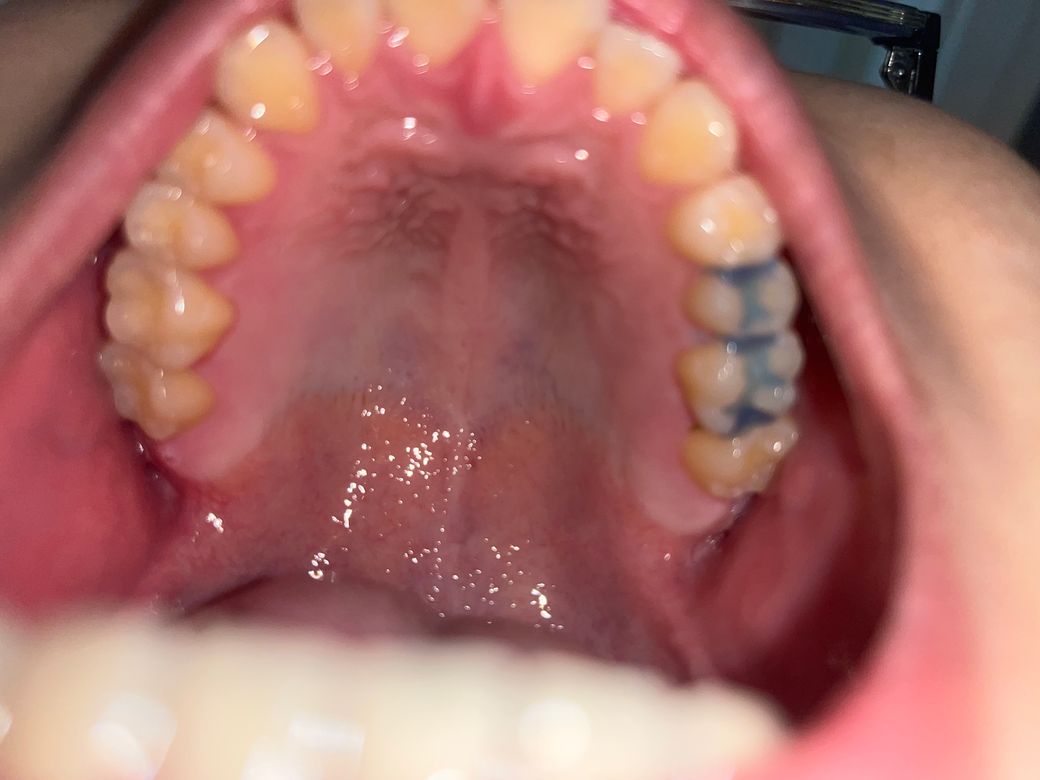

인레이로 임시재료를 했는데 2곳을 해서 한곳은 있는데 다른쪽 끝부분이 있는지 모르겠어요 있는지 알고싶어요 잘 있는건가요? 아니면 살짝 떨어진건가요

인레이 치료를 하고 임시재료를 넣어 놓은곳은 파란색으로 보이는 부분입니다. 떨어지거나 그렇진 않은것같습니다.

인레이 치료 임시재료의 형태를 봤을 때에는 특정 부위가 떨어져 나간 것으로 보이진 않습니다.

인레이를 하고 부착을 하는 임시 수복물은 보통 파란색을 뜨고 있습니다. 따라서 탈락이 되었을 경우 파란색이 없어지기 때문에 육안으로 확인하기 쉽습니다.

사진 상으로는 파란색 임시재료가 치아 2개에 모두 잘 적용되어 있는 것으로 보입니다. 걱정하지 않으셔도 될 듯 합니다.

사진상 아주 확실하진 않지만 잘 붙어있는 것 같습니다 보통 임시재료 떨어져있으면 아주 시립니다